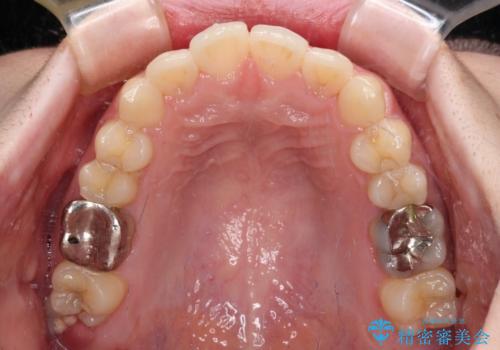

- 上下歯列全体のデコボコを気にして来院された患者様です。

主に下顎歯列全体の後方移動とIPR(歯と歯の間を削る)によってデコボコが解消するように設計し、インビザラインにより治療を行うこととしました。

1年半程度で終了するのではないかと予想しましたが、途中1年以上の来院がなく、トータルで3年の時間がかかってしまいました。

前歯のデコボコはより改善することが望ましい状態でしたが、患者様の希望により終了することとなりました。